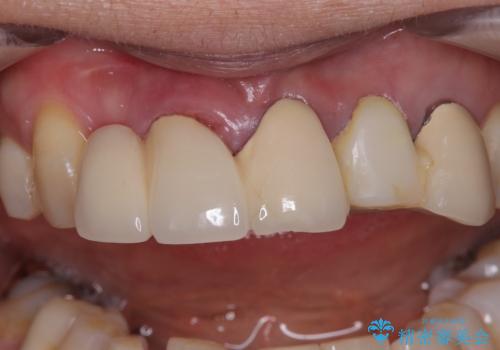

不具合の多い前歯 オールセラミックブリッジ治療

- 前歯のブリッジに違和感を感じるとのことで来院された患者様です。

受け口を無理やりブリッジで改善したことで、支台歯の1本は歯根が破折しており抜歯が必要な状態でした。

根管治療がされている歯の一部には根尖部の違和感があり、根管治療が必要と判断されました。

抜歯および根管治療を実施した後にオールセラミッククラウンにて補綴することとしました。